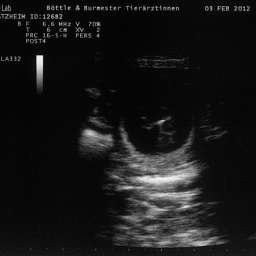

3.2.2012, 32.Tag: Der Ultraschalltermin ist vollbracht: Juhu, wir werden Eltern!!!

Aus Herzklopfen wurde Herzrasen und dann endlich, kurz vor der Herztablette, zeigte uns der Ultraschall 5 KLEINE WUNDER, gesunde Fruchthüllen, mit lebendigem Innenleben und pochendem Herzen. (...passte sehr gut zu unseren...)Wieviele es letztendlich werden, bleibt eine riesige Überraschung.

Bitteschön, ein kleines Filmchen mit dem Titel: "5 auf einen Streich, oder wie es in den Bauch hineinschallt, schallt es auch wieder hinaus."

4.2.2012, 33.Tag: Hier sind also die Fotos der kleinen Flauschmonster in ihren Höhlen.

Sucht Euch doch schon mal einen aus: